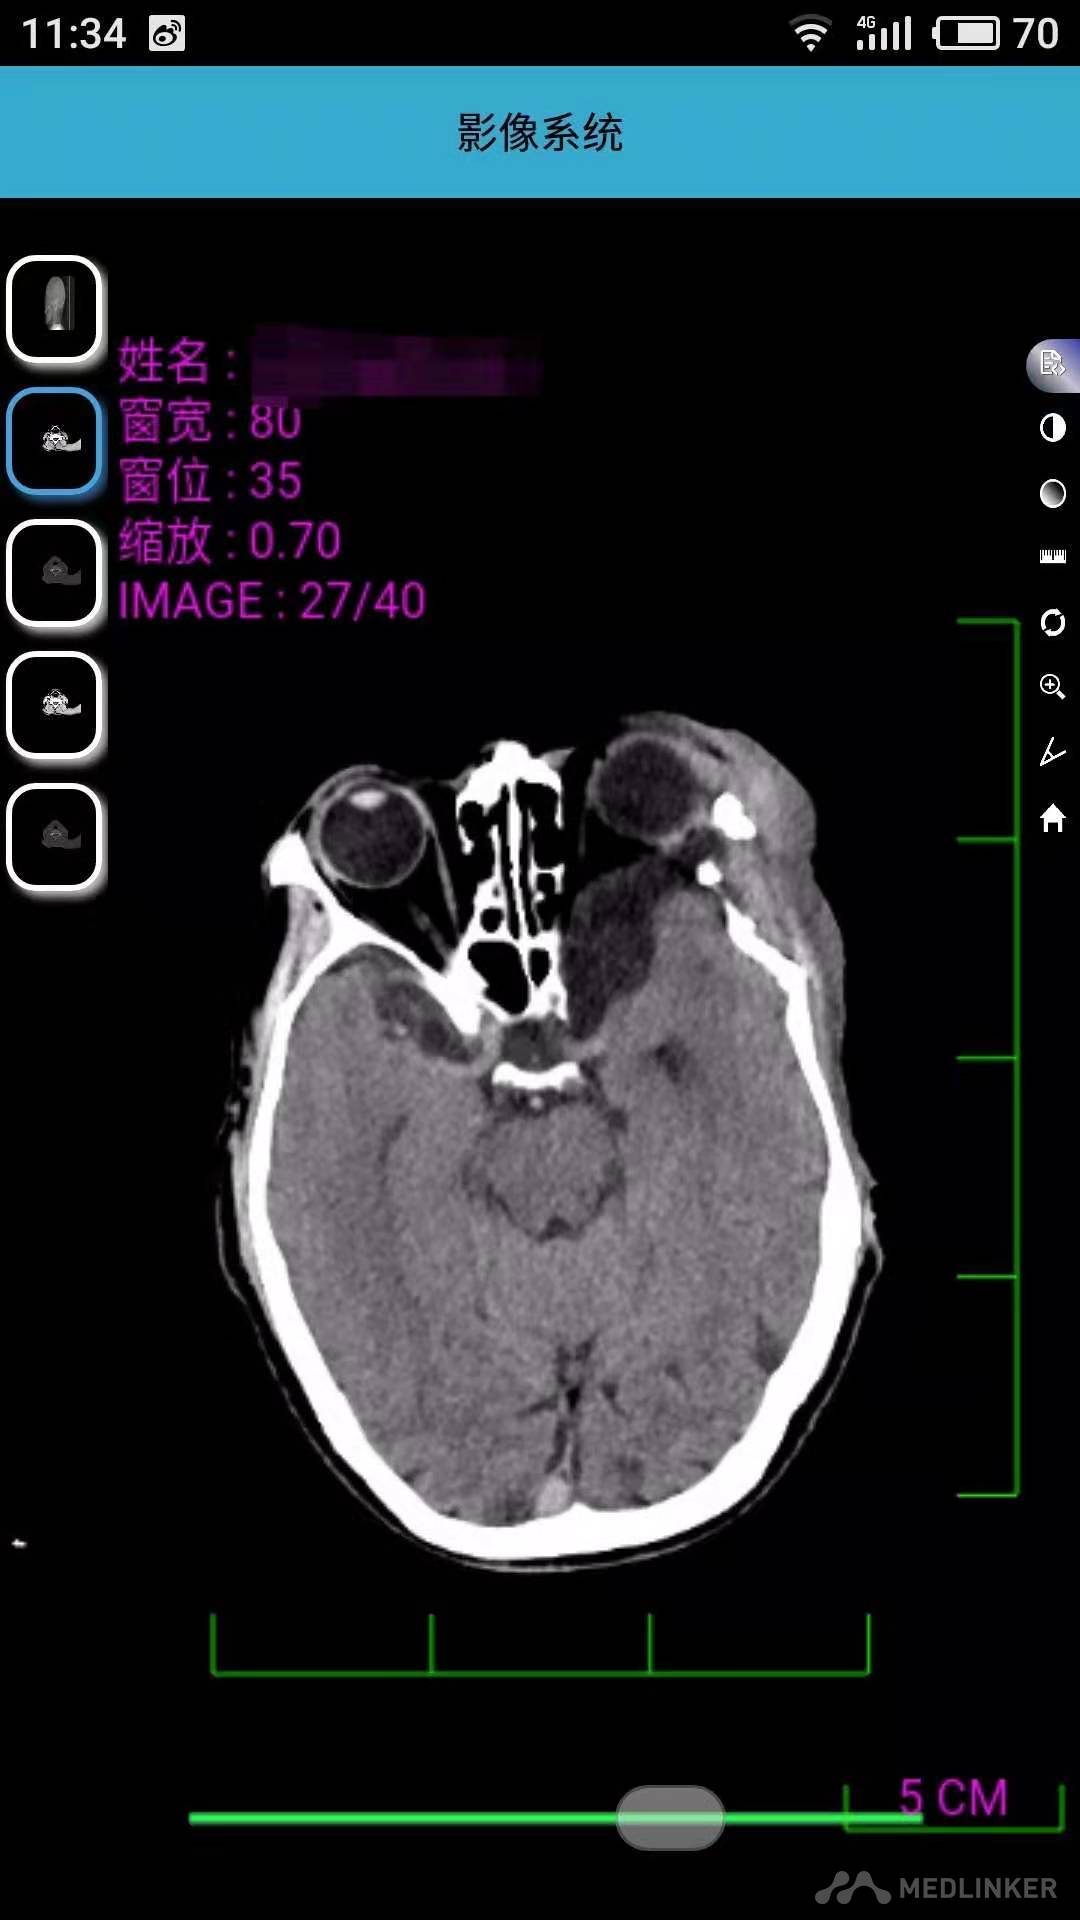

面部左右不对称,比例不协调,左侧上睑下垂,眼球动度异常,对光反射及调节反射不灵敏,左侧面部大面积棕色斑,左侧面部15cm*10cm肿物,边界清,活动度可,质地软,皮温正常,触痛阴性,胸部、腹部及背部多发散在肿物凸起。具体见图。CT示左侧颞骨及眶外侧壁局部骨质不连续,左侧颞极蛛网膜间隙增宽并部分突入颞部肌间隙内,左眼受压旋转。